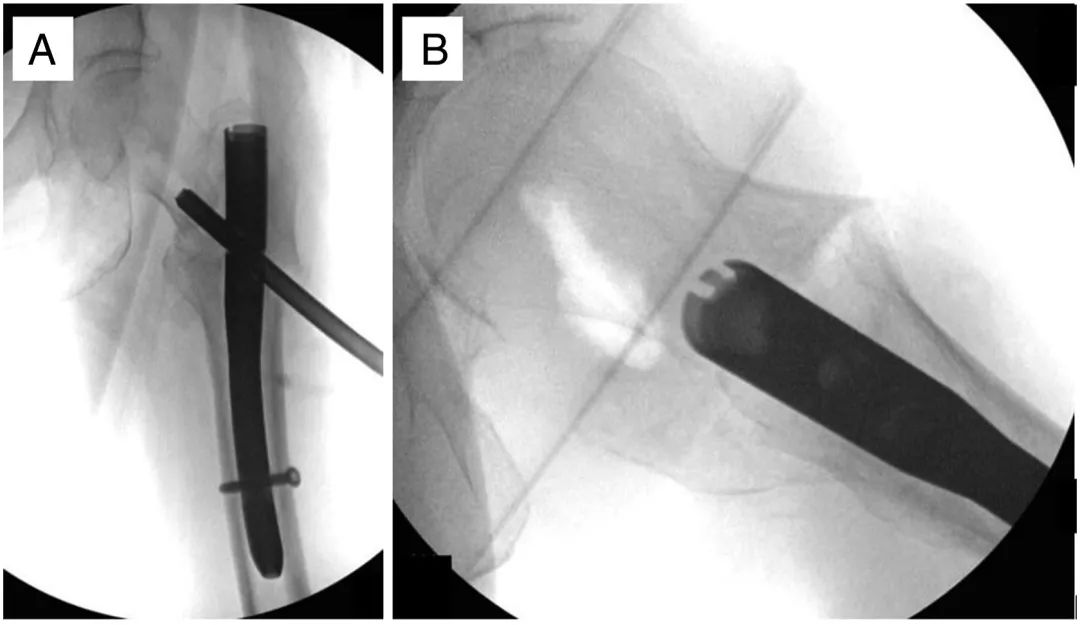

Une incision transversale de 1 à 2 cm est ensuite pratiquée à travers le fascia iliotibial (ITB).Le clou à tête d'origine est retiré à l'aide d'un guide fileté inversé (Figure 3).Dans le cas d'une perforation de la tête fémorale, un guide creux avec une vis de blocage distale est utilisé afin d'éviter les fuites de ciment dans l'articulation (Figure 3A).Plus précisément, la matrice a d'abord été injectée après le retrait des deux couches externes de la triple canule, puis placée dans la zone perforée en réinsérant les deux couches externes.

Figure 3, Images peropératoires antéropostérieures (A) et latérales (B) d'un autre patient montrant une tête fémorale avec une greffe de défaut osseux interstitiel.